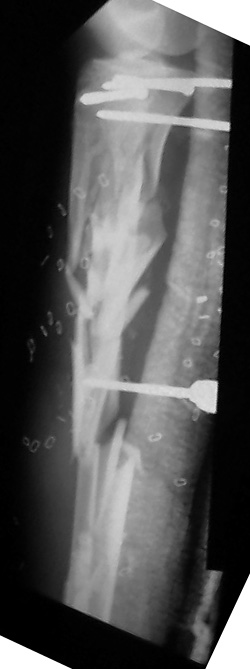

Tibia Fx ForumCase 1

I would appreciate treatment suggestions.My patient is a 30 year old with a very comminuted tibia fracture 6 weeks ago.It was grade 3B open. Initial treatment included irrigation, debridementClick images to enlarge.

and a hybrid external fixator including femur, tibia and foot. Screwswere placed in the plateau and plafond and a free flap plus STSG. Theskin is ok but atrophic. The femoral pins were removed and knee motionstarted at 6 weeks. There is no sign of callus. There is one pin inthe one large fragment of the diaphysis. All the pieces are lined upreasonably well. The XF pins are ok. Suggestions? Thank you.

Date: Thu, 14 Dec 1995 17:48:46From: hwb@eideti.com (Bill Burman)Of course what I have to say has to be taken with a mountain of salt as Ihave not practiced orthopaedics for 5 years.What I would do at this point is hike out the 5 mm diaphyseal pin. I can'tbelieve it is doing much. I would wait a few more weeks for that pin tractto properly clean itself and seal up. Hopefully it has not been infected.At that time I ought to have pretty good consolidation of themetaphyseal-epiphyseal fractures. I would remove from the ends of the boneany hardware which would block the placement of a reamed interlockingtibial nail. Large reduction forceps and possibly strategically placedsteinman pins would be used to protect against the possibilty ofmetaphyseal-epiphyseal refracture during nail placement. The nail needs tobe carefully started as high as possible and more lateral than usualbecause of a valgus tendency for nailings of proximal tibia fxs.If at this time, I did not see much in the way of diaphyseal callus thenprior to nail placement, I would try to do a closed intramedullary iliacbone grafting with chest tube ala Chapman, JBJS 62A 1004 1980. I realizethis technique was meant for segmental defects of the femur but this mightbe an application for it as well. If I couldn't get much graft in this way,I would put it in posterolateral - if that did not jeopardize the free flapin some way.*****************************From: EDCCYANG@aol.comDate: Thu, 14 Dec 1995 22:16:30 -0500You are to be commended for what you've done so far. It sounds like thetibia is well aligned and the soft tissues are healed. Now you just have toget the bones healed.I have extensive experience with the hybrid exfix but never have I seen atibia this shattered. (or maybe once)Now I would try the exogen unit, if you have not done so already. This isthe ultrasound device which has been working great for us! Their telephone# is 1-800-836-0849.I would hold him in the external fixator as long as the pins are clean.Hopefully, some of the fractures will heal and you can deal with only one ortwo nonunion sites. Consider plating the fibula and getting the fibulahealed, either simultaneously with a fib-pro-tib operation, and /orposterolateral bone graft. I have done all of the above to get tibiae toheal.Edward Yang, MDElmhurst HospitalMount Sinai****************Date: Fri, 15 Dec 1995 10:21From: Jeffrey Anglen Bill, for a guy who hasn't practiced clinically for 5 years, you seem tohave a pretty good grip on treating tibia fractures. The only thing I woulddisagree with is conversion to an intramedullary nail after this period oftime. I would be too afraid of intramedullary infection from a pin site,even if the pin sites looked OK. I don't know if the risk is the same withhybrid fixators as it is with traditional half-pin fixators - that might makean interesting study - perhaps someone with more experience withhybrid fixators has a better feel for the relative risk between pin andwire sites.I would continue with hybrid fixation, a little weightbearing and earlybone graft of the diaphysis posterolaterally. I have no experience withthe accordion technique.How about you guys at Harborview? Any thoughts on this tibiafracture?****************Date: Sat, 16 Dec 1995 11:45:10 +0530 (IST)From: "Dr.ML Parihar" the accordion manouevre does not work. to my knowledge this is nowuniversally accepted, especially in the treatment of non-unions. anyonedisagree?for a comminuted fracture of the tibia why not consider atibia-pro-fibula grafting as described by harmon. while on the subject ofbone grafting i would like to hear fromsurgeons who have used bone marrowinjections for the treatment of nonunion or delayed union.how much to be aspirated? from where?where do you inject? into the fracture site or in a cuff fashion aroundthe fracture site? Dr. Mangal Parihar**************************Date: Sat, 16 Dec 95 22:04:09 +0500From: "Alexander N. Chelnokov" Hi> I have not received any further comments/suggestions on the comminuted> tibia case since posting the images of the xrays. There has been> considerable useful discussion of posting images to be easily viewed> in various manners.Sorry but I missed when you pointed the name and location of the image so plsrepeat...> I did institute the "accordion" technique of .25 mm compression at> 6 am and noon; then .25 distraction at 6 pm and midnite.We use another schedule - 2 weeks of distraction 0.5mm/day and then2 weeks of compression 1 mm/day...> I also started 10 pound weight bearing.I do not limit weigth-bearing. More exactly, patient should load his legas he can. In case of extra-articular fractures of course.> I'd like to bone graft it but I'm not sure> where to put the bone graft because there are so many pieces.Do think about marginal corticotomy and slow tension of fragments to bridgegaps?*************************Date: Sun, 17 Dec 95 21:45:18 -0600From: "Andrew H. Schmidt" After seeing the images, I congratulate Tom on his management of the casethus far. Our general philosophy at Hennepin County is that once externalfixation is chosen as the treatment, it should be continued to union. Whenpossible, we will convert to a nail within the first couple of weeks, butnot beyond this because of the concern for infection.In my experience with either plateau or plafond fractures plus diaphysealextension, the metaphyseal fractures heal and it is the diaphysealcomponent that requires grafting. I have several times removed the hybridfixator, curretted the pin sites, performed an open autogenous grafting,and reapplied a new half-plane unilateral fixator to the diaphysis. Ofcourse, if the hybrid frame was still needed I would not replace it.However, I find the circular hybrid frames to be such a hassle to take careof, and the patients dislike them so much, that if the juxta-articularfractures are healed, I go ahead and convert to a simpler fixator. So, that remains my two-cents worth, which I thought I'd post to the wholegroup this time since this case has sparked so much interest.AndyAndrew H. Schmidt, M.D.Staff Physician, Hennepin County Medical CenterClinical Instructor, University of Minnesota******************************Date: Tue, 19 Dec 1995 12:31:57 -0500From: hwb@eideti.com (Bill Burman) I see from the discussion that perhaps I am too aggressive and need tolearn how to relax.I am learning some new things here. Dr. Ed Yang made a plug for ultrasoundstimulation - Exogen. Here is the abstract of an article published in theJ Bone Joint Surg Am 1994 Jan;76(1):26-34 by the San Antonio group(Heckman, Ryaby, McCabe J, Frey JJ, Kilcoyne RF). The study was paid forby Exogen.TI - "Acceleration of tibial fracture-healing by non-invasive, low-intensity pulsed ultrasound."AB - "Sixty-seven closed or grade-I open fractures of the tibial shaft were examined in a prospective, randomized, double-blind evaluation of use of a new ultrasound stimulating device as an adjunct to conventional treatment with a cast. Thirty-three fractures were treated with the active device and thirty-four, with a placebo control device. At the end of the treatment, there was a statistically significant decrease in the time to clinical healing (86 +/- 5.8 days in the active-treatment group compared with 114 +/- 10.4 days in the control group) (p = 0.01) and also a significant decrease in the time to over-all (clinical and radiographic) healing (96 +/- 4.9 days in the active-treatment group compared with 154 +/- 13.7 days in the control group) (p = 0.0001). The patients' compliance with the use of the device was excellent, and there were no serious complications related to its use. This study confirms earlier animal and clinical studies that demonstrated the efficacy of low-intensity ultrasound stimulation in the acceleration of the normal fracture-repair process."Also, Dr. Parihar mentions bone marrow injection. In CORR 313 8-18, 1995,Dr. John Conolly of Orlando, FL writes :TI - "Injectable Bone Marrow Preparations to Stimulate Osteogenic Repair."AB - "The great versatility of bone marrow transplants based on stem cellactivity has been demonstrated successfully for a variety of previouslyuntreatable hemopoetic conditions. Autologous bone marrow delivered bypercutaneous injection or by a direct transplant as a composite graft alsohas proven effective for osteogenic stimulation in a series of 100 skeletalhealing problems, including delayed unions and nonunions of fractures,arthrodeses, and bone defects. The efficiency of marrow to form bone can beincreased by a number of methods, including differential centrifugation andcomposite grafts of marrow with demineralized bone matrix and othercarriers or stimulatory factors."Dr. Connolly concludes his article by saying :"Marrow and marrow composite grafts, in this author's experience during thepast 8 years, essentially have eliminated the need for open harvesting anddelivery of autologous bone grafts to stimulate osteogenic repair ofdelayed unions, nonunions, arthrodeses and bone defects."Any references for the Ilizarov "accordion maneuver"?***************************Date: Tue, 19 Dec 1995 14:11:27From: hwb@eideti.com (Bill Burman)I am transmitting another opinion received via the HWB BBS fromDr. Joldas KuldjanovVisiting Professor at Detroit Medical CenterProfessor of Orthopedics & TraumaUniversity of Tashkent, UzbekistanRe: comminuted tibia fxThus far, there appears to be no sign healing because of local factors, thehigh energy of trauma, stripping of periosteum, soft tissue damage and poorcontact of bone. I would have initially fixed the fracture with a four ringIlizarov fixator. 2 rings in metaphyseal zones (distal and proximal) and 2rings in the diaphyseal region for the purpose of interfragmentarycompression.The location of wound and soft tissue damage is unknown to me. It is mostlikely anteromedial ?At this point, I would perform open reduction and internal fixation offibula with a long semitubular plate. I would add 2 more rings to thefixator to bring about reduction and interfrag compression of the tibialcomminution. The type of fixator is immaterial but interfrag compressionwould be accomplished by olive wires. Also, I would add bone graft andplacement of this would be in accordance with the location of soft tissuedamage. Weight bearing should be as tolerated and there should be cautionabout the possibity of equinus. I am not too worried about pin tractinfection. These smaller pins can be easily replaced. I would use theaccordion technique in the event of atrophic non-union.Best regards and best wishes with the management of this very difficult case.***********************Date: Tue, 19 Dec 1995 22:03:13 -0500From: OTS1@aol.com RoyI am somewhat amazed at all this discussion, but find it fascinating. Iwould treat this guy to completion with the circular frame until thearticular and metaphyseal components healed. Unfortunately, you would get amal-/non-union at the diaphysis which would preclude the use of a later nail,unless you took it all down. If you needed to do that I would then just platehim with a long 18 - 22 hole 4.5 narrow DC plate on the medial side. Thiswould obviate the risk for infection. Furthermore you could graft at the timeof plating. So what's the big deal? Routine case,... right?Anyway, Exogen is too new to try, and Connally's study is severely flawed,too many variables, no controls, hypertrophic nonunions rodded and thenmarrow injected, nonunion healed. Don't you think it would have healedwithout the injection? Of course it would have! Anyway, I like this format.Anyone going to Russia?***************************From: "Alexander N. Chelnokov" Date: Wed, 20 Dec 95 06:51:16 +0500Hi> Also, Dr. Parihar mentions bone marrow injection. In CORR 313 8-18, 1995,> Dr. Connolly concludes his article by saying :>> past 8 years, essentially have eliminated the need for open harvesting and> delivery of autologous bone grafts to stimulate osteogenic repair of> delayed unions, nonunions, arthrodeses and bone defects.";) Told like about Ilizarov.> Any references for the Ilizarov "accordion maneuver"?I used it last years... It really works.But for the case maybe better would be to add partial corticotomies andperform closed slow "bridging" by the fragments.About reference... This must be accessible for you:TI: Clinical application of the tension-stress effect for limb lengthening.AU: Ilizarov-GAAD: Kurgan All-Union Center for Restorative Traumatology andOrthopaedics, USSR.SO: Clin-Orthop. 1990 Jan(250): 8-26AB: For 40 years, the author has been developing a system oforthopedics, traumatology, and limb lengthening using a circulartransfixion-wire external skeletal fixator, often in combination withbiomechanic methods of stimulating the formation of new osseous tissuewithin a widening osteotomy distraction site. The factors important forneoosteogenesis after osteotomy include: maximum preservation ofextraosseous and medullary blood supply; stable external fixation; adelay prior to distraction; a distraction rate of 1 mm per day infrequent small steps; a period of stable neutral fixation afterlengthening; and physiologic use of the elongating limb. For asuccessful fixator application, the apparatus must be applied withconsideration given to the number, size, and location of the rings, theplacement and tension on the wires, the technique of wire insertion, theeffect of soft-tissue transfixion on limb use, and the prevention ofbone and joint deformities caused by countertension in soft tissues.Clinical application of the author's techniques permits stature increasein certain forms of dwarfism, correction of deformities and limb-lengthinequalities, and stump elongation. For many of these applications,motorized distraction can provide continuous limb lengthening while theapparatus is on the patient. Best regards, Alexander N. ChelnokovUral Scientific Institute of Traumatology and Orthopaedicsstr.Bankovsky, 7. Ekaterinburg 620014 Russia********************Date: Thu, 21 Dec 1995 12:46:14 +0530 (IST)From: "Dr.ML Parihar" On Wed, 20 Dec 1995, Alexander N. Chelnokov wrote:> > Any references for the Ilizarov "accordion maneuver"?>> I used it last years... It really works.> TI: Clinical application of the tension-stress effect for limb lengthening.> AU: Ilizarov-GAfor a start lets try to define what we mean by the 'accordion maneuver'.i have heard it used to talk about alternating cycles of compressiondistraction in the same day, compression for a preiod of 1 or more weeksfollowed immediately by distraction for an equal duration; and also forcompression followed by a rest period and then a period of distraction.though the articles from kurgan talk about successes with the 'accordionmaneuver', most other surgeons that i have had occasion to meet eitherpersonally or at meetings have not found it to be a useful maneuver inatrophic nonunions which is what it 's use is advocated for.i personally have not had any experience with it. Dr. Mangal Parihar************************Date: Sat, 23 Dec 95 10:52:54 CSTFrom: kenneth.d.johnson@mcmail.vanderbilt.eduThis message was originally written on Dec.18, who knows where it has been?Congratulations on a job well done to date. Hopefully the leg is straight and clean, and the proximal metaphysis fracture is now healed. Now comes the time to think! I agree with others, a nail would not be advisable at present. Perhaps the ultrasound would help, it certainly shouldn't hurt! No experience here. Personally, I think the fixator and posterolateral bone grafting is your best bet. With the proximal fracture you would have to arthrodese the proximal tib-fib joint. I can't appreciate the x-ray well enough to see how far down the bone graft would need to go but you could go as far as the distal tib-fib joint. Perhaps within 6-8 weeks of grafting you could consider removing the fixator and using a cast. Also if the amount of graft is a question or better a problem, one could consider the use of Colagraft to augment the usual autogenous cancellous bone graft.I can say though that I am glad that it is you and not me!KDJ ***********From: hwb@eideti.com (Bill Burman)Date: 12/21/95 6:58 PMAlexander,Maybe I am missing something but I have re-read :>TI: Clinical application of the tension-stress effect for limb lengthening.>AU: Ilizarov-GA>AD: Kurgan All-Union Center for Restorative Traumatology and>Orthopaedics, USSR.>SO: Clin-Orthop. 1990 Jan(250): 8-26and cannot find specific reference to the efficacy of the "accordion"technique for atrophic nonunion. Are there any series in the Russianliterature which compare the "accordion" technique to controls or othertreatment methods of nonunion ?************************Date: Wed, 20 Dec 1995 18:34:33 -0700 (MST)From: TDECOSTE@medusa.unm.eduI'd like to get Dr. Kuldjanov's email address but can't decipherit from the message I received.His suggestion for additional diaphyseal wires and rings is mostappealing to me but I'm not sure which pieces of diaphysealcomminution would be appropriate.Tom DeCoster. Merry Christmas****************************Date: Sat, 23 Dec 1995From: hwb@eideti.com (Bill Burman)In reply to Dr. Tom Decoster's request for more specifics, Dr. Joldas Kuldjanov from Detroit Medical Center has faxed to the HWB Foundation a diagram of a preoperative plan illustrating the placement of additional rings and olive wires for posting with the discussion of this case at :http://www.hwbf.org/hwb/